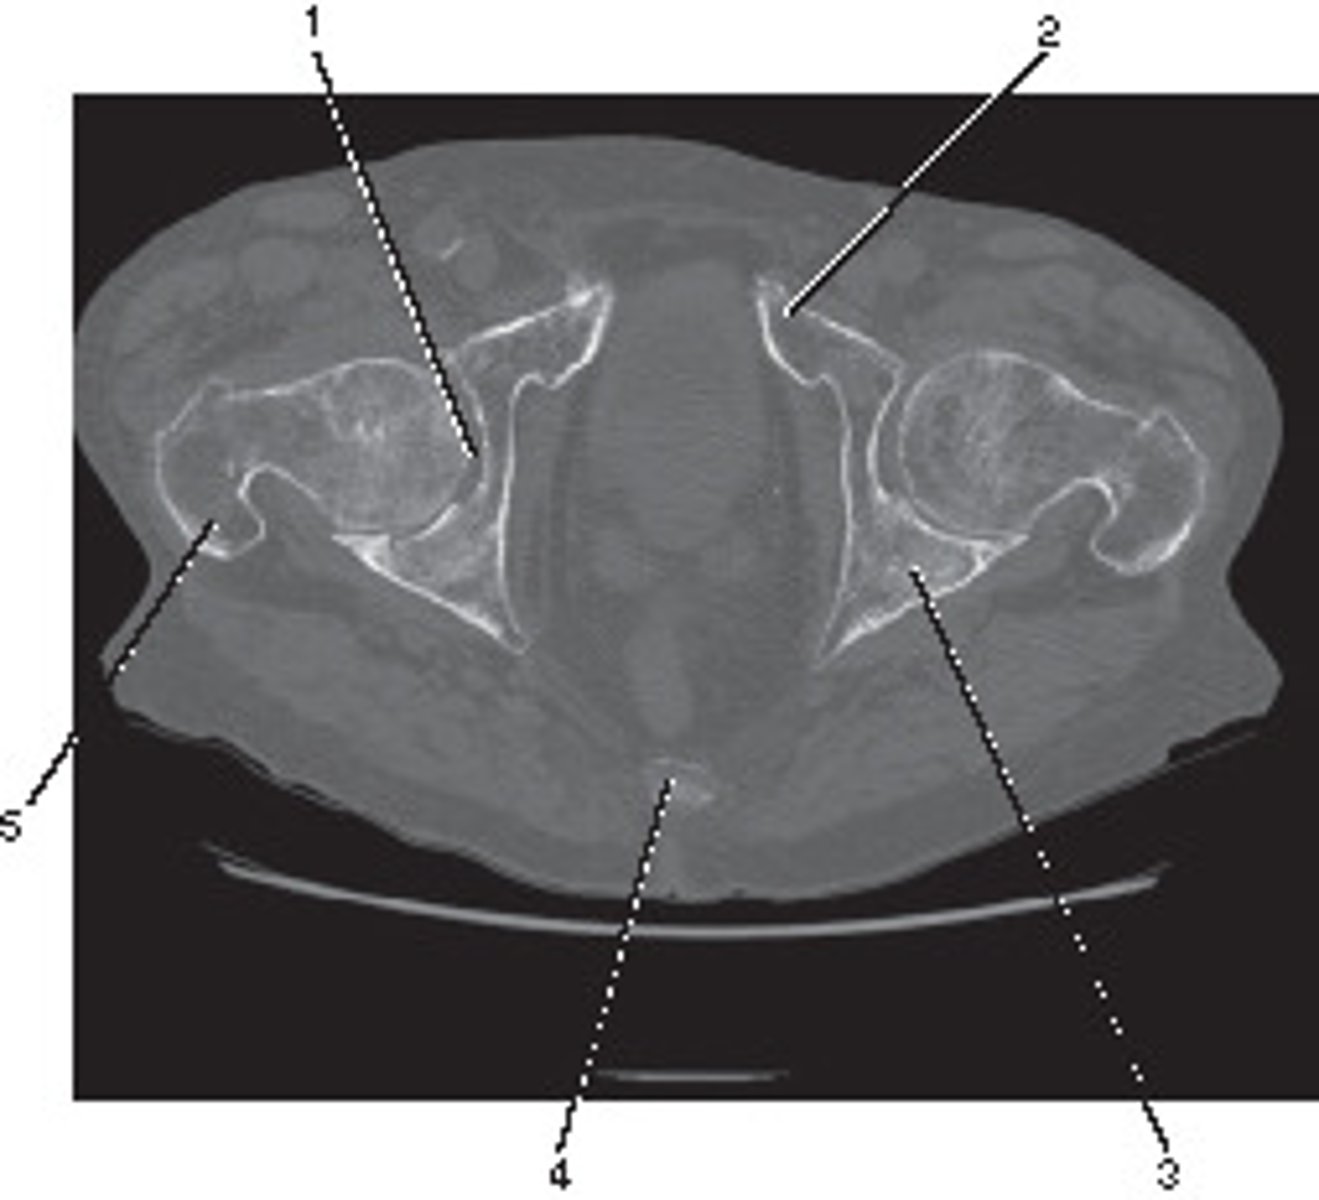

What number corresponds to the acetabulum?

<p>What number corresponds to the acetabulum?</p>

Ilium

Number 4 corresponds to which of the following?

<p>Number 4 corresponds to which of the following?</p>

Coccyx

Number 1 corresponds to which of the following?

<p>Number 1 corresponds to which of the following?</p>